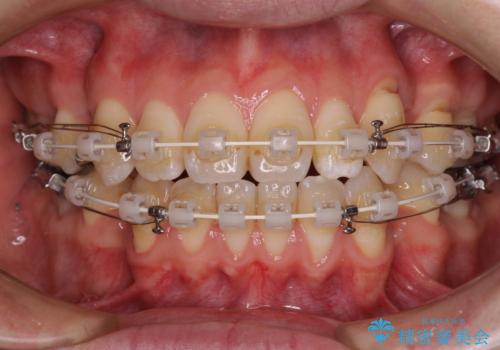

- 矯正装置

- 審美装置

装置は、透明感のあるクリアブラケットとホワイトコーティングされたワイヤーを使用した、目立ちにくい審美装置を選択。

周囲に気づかれにくく、日常生活にも自然に溶け込みます。